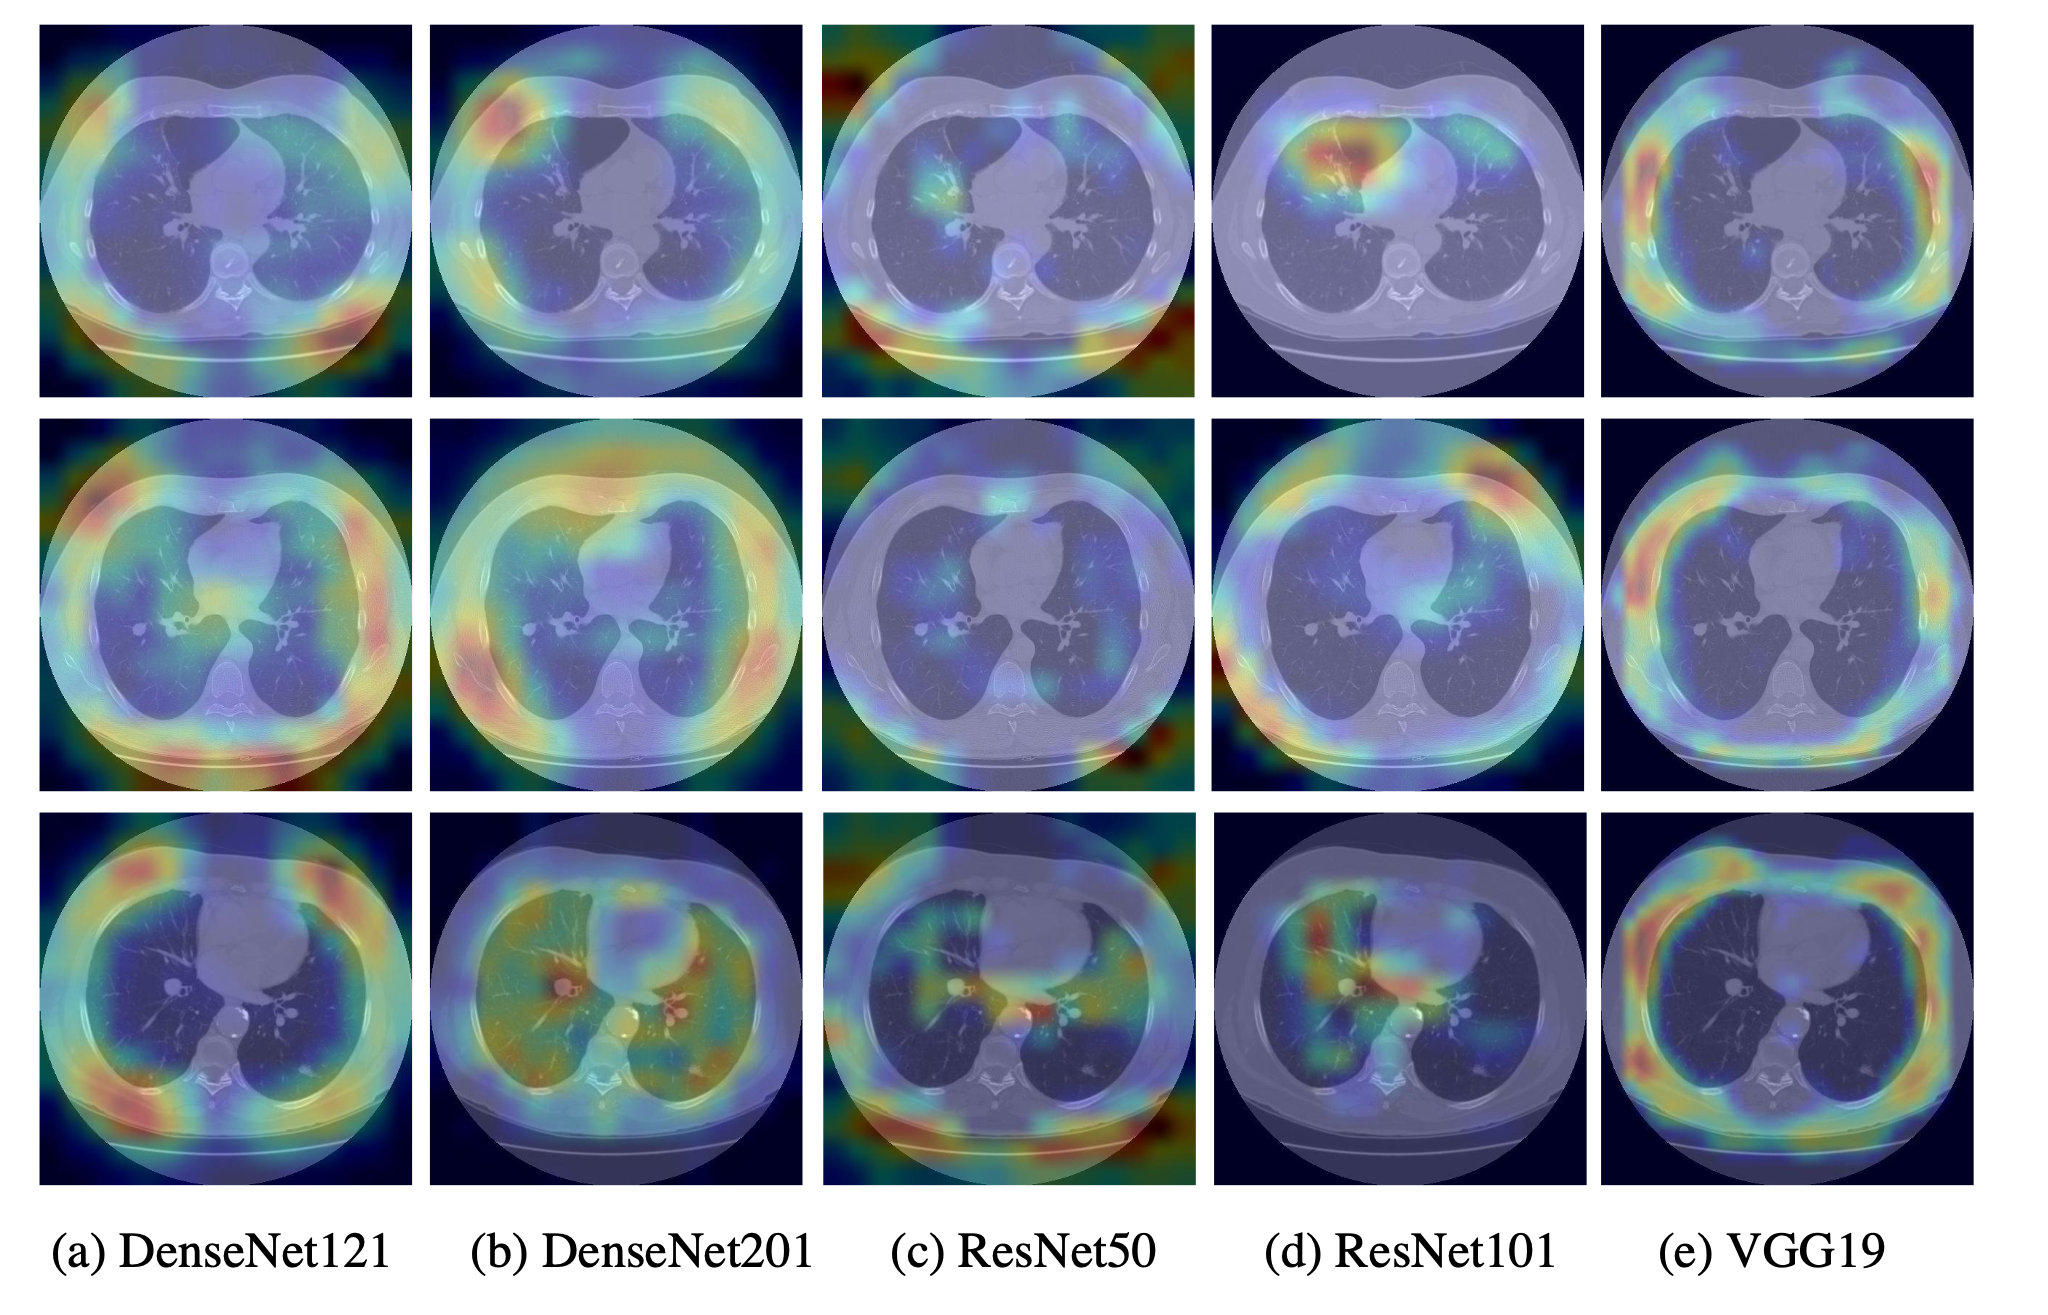

Gradient-weighted class activation mapping (Grad-CAM) is applied on deep learning models to clearly interpret the prediction results and provide an explainable visual (Gite et al.,, 2022). Grad-CAM, introduced by Selvaraju et al., (2017), uses the gradient of any target concept and places it in the final convolution layer to generate a coarse localization map that highlights the key regions in the image to predict the required concepts, which can be used to help users establish appropriate trust in predictions based on deep networks. Figure 3 shows the Grad-CAM visualization applied to the first column of Figure 1 using 5 deep learning models. The overlaid heat-maps indicate increasing model prediction confidence from 0.0 to 1.0. As we can see, the regions of abnormalities are localized in some models. But irrelevant regions are also included by almost all models, which lead to unsatisfactory results.